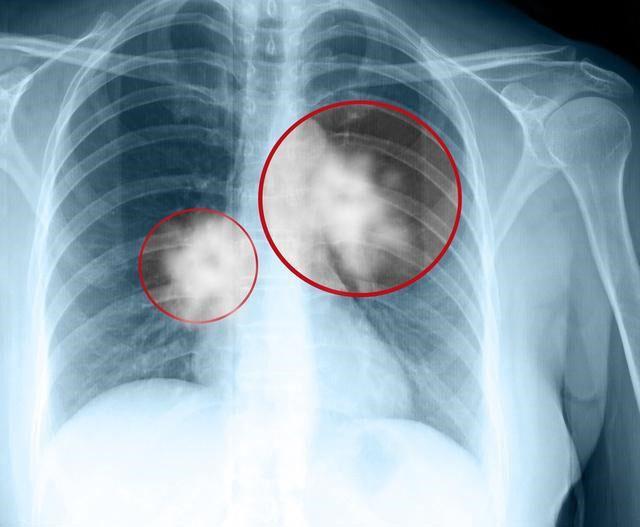

肺癌晚期了,家庭条件又不好,还有必要治疗吗?这个问题恐怕不同的人有不同的回答,不仅仅涉及到金钱的问题,还有亲情的因素。当生命即将结束,每个人都有强烈的求生欲望,绝大多数病人和家属都希望使用一切办法延长生命,也有少数家庭会因为意见分歧而反目成仇。

从年龄来讲,如果年龄很大,基础疾病多,体质不好,积极治疗的意义确实不大,但最基本的治疗,比如止痛、适当的营养治疗还是需要的。从疾病本身来讲,肺癌晚期并不意味着生命马上要终结,比如颈部淋巴结转移,纵隔淋巴结转移也是晚期,但短期内并不危及生命,这时候即便家庭条件不好,在体质允许的情况下还是需要做一些化疗或者放疗,尽量延缓疾病发展,现在大家都有医保,选用国产化疗药报销之后花费都不高。从经济的角度,如果家庭条件不好,肺癌晚期病人确实最好不要选择昂贵的进口药、靶向药和免疫治疗药物。人财两空、因病致贫是任何人包括医生都不愿意看到的结局,毕竟有限的金钱需要留一些给活着的人生活。从治疗效果来说,肺癌晚期治愈的机会微乎其微,这个每个人都是清楚的,但确实有部分幸运的病人寿命能延长很多年,临床上遇到过延长7-10年的病人,这其中印度靶向药和原料药起了一定的作用,所以如果条件不好,有基因突变的肺癌晚期病人可以试试印度版靶向药,过早的直接放弃治疗比较可惜。